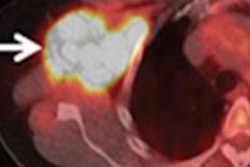

Results from FDG-PET/CT scans can greatly influence decisions regarding treatment and surgery for patients with metastatic melanoma, according to a study from Eberhard Karls University Tübingen in Germany.Lead author Dr. Christina Pfannenberg, an associate professor in the department of radiology, and colleagues wrote that one key factor is the proper selection of patients for a complete metastasectomy, which can lead to increased long-term survival.

FDG-PET/CT results changed therapy in more than 50% of the patients, including a major shift in strategy to surgery in more than 40% of the cases, the group found. The greatest number of changes was among patients in the primary staging group. In addition, approximately 30% of those in the restaging group had their treatment plans altered.

Most interestingly, among more than a dozen patients who were scheduled to have a metastasectomy based on CT alone, PET/CT excluded metastases in a majority and discovered further metastases in several other patients.